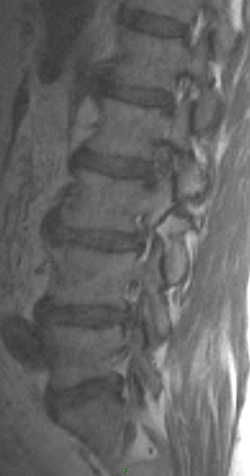

There is evidence of a grade 1 anterolisthesis of L3 on L4. The second set of images show non acute bilateral pars fractures at L3, responsible for the anterolisthesis.

The patient has an isthmic spondylolisthesis of L3. This is a unique case in that L5 is by far the most common location for this type of spondylolisthesis, with L4 less common, and L3 even more uncommon.